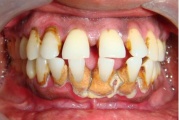

Krooniline parodontiit

Krooniline parodontiit on mikroobide poolt põhjustatud hammaste tugikudede põletik, mille tulemusena tekib progresseeruv alveolaarluu (nähtav röntgenograamil) ja periodontaalligamendi destruktsioon, igemetaskute moodustumine, igeme retsessioon või mõlemad kahjustused kombineeritult. Loe edasi »

Sümptomid:

- igemed veritsevad (19)

- igemed punetavad (21)

- ige on paistes (mädapunn)

- igemed on tursunud/vohavad (17)

- puudulik suuhügieen (5)

- igemepealne hambakivi (5)

- igemealune hambakivi (4)